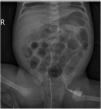

A los 14 días de nacer, presentó anemización (hemoglobina: 7,7g/dl; rango normal: 12,5-20,5), por lo que se administró IVIG (1g/kg iv en 6h). La paciente permaneció hemodinámicamente estable antes y durante el tratamiento. Se detectó progresión de la anemia a pesar de la infusión de inmunoglobulinas (concentración de hemoglobina de 6,7g/dl 12h tras su administración), por lo que se realizó exanguinotransfusión parcial (80cc/kg) mediante vía venosa central (vena femoral izquierda). No hubo eventos adversos durante la transfusión. La concentración de hemoglobina aumentó a 12,3g/dl (fig. 1). A las pocas horas de concluir la exanguinotransfusión, la paciente mostró deterioro general con distensión abdominal y vómitos biliosos. Requirió intubación endotraqueal y soporte hemodinámico con dopamina. La radiografía abdominal era indicativa de ECN (fig. 2). Se llevó a cabo una laparotomía urgente, confirmándose el diagnóstico. Se practicó escisión del íleo distal y el colon ascendente con creación de una ileostomía terminal. Tras la operación, la paciente se recuperó progresivamente y fue dada de alta a los 30 días.